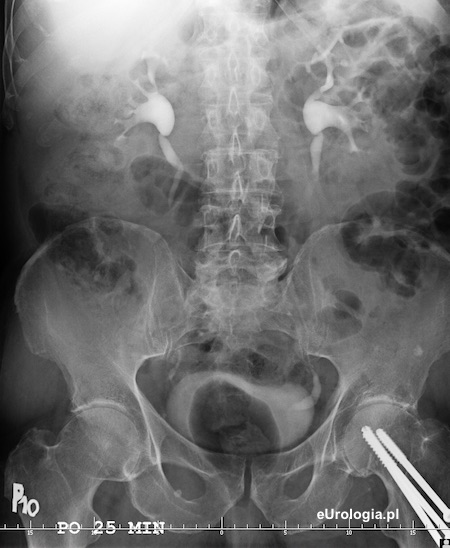

Cystogram przesłoniety przez gaz w jelicie grubym. Widoczne zakontrastowanie dolnego odcinka lewego moczowodu